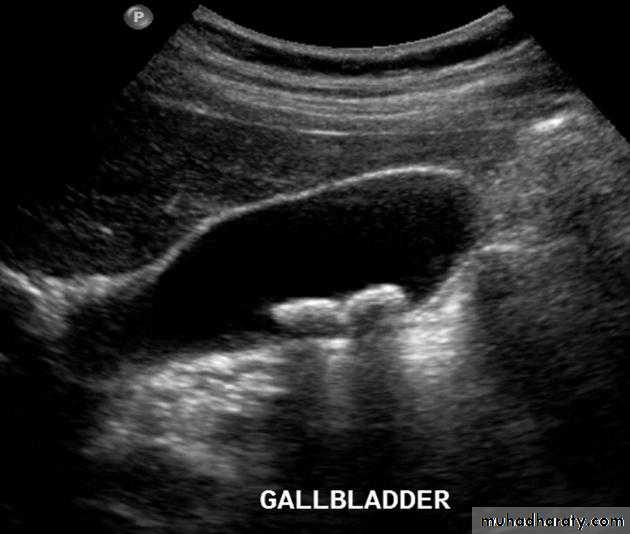

Gall stones

Gall stones are more frequent in middle age females. 20% of gall stones are visible on plain film. On US, stones are strongly echogenic with acoustic shadow(which is not seen with polyps). US is not reliable for detecting stones in CBD which are better demonstrated by MRCP

Cholecystitis

US features of early or uncomplicated acute cholecystitis:1.gall stones (which may be impacted in the GB neck or cystic duct)

2.gall bladder wall thickening

3.gall bladder distension

4.positive sonographic Murphy's sign (focal tenderness over the GB when compressed by the US transducer)

US features of advanced or complicated acute cholecystitis:

1.pericholecystic fluid collection

2.striated appearance of the thickened GB wall

3.intraluminal membranes caused by sloughed GB mucosa

4.gas in GB wall or lumen resulting in emphysematous cholecystitis

US features of chronic cholecystitis are thick wall and GB contraction